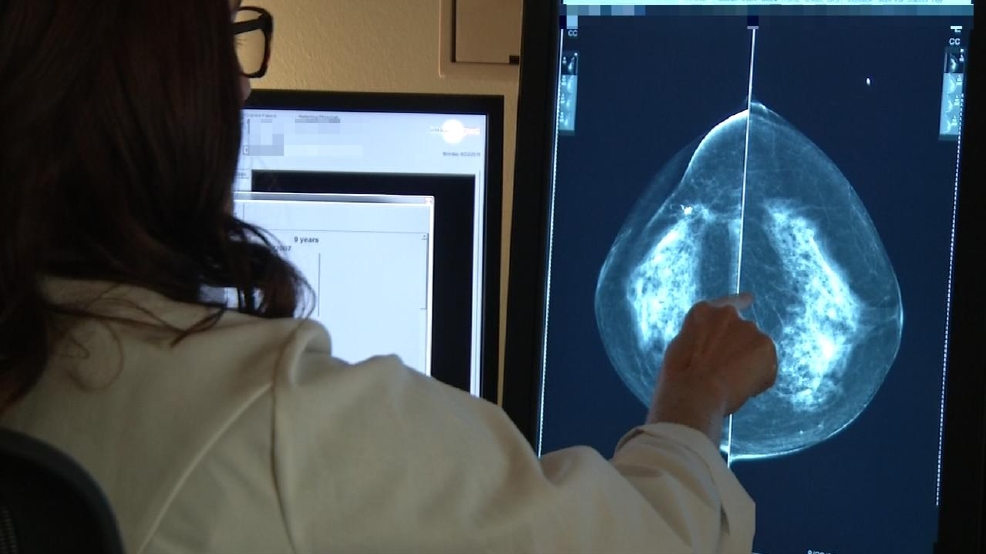

Breast cancer is the most common cancer in women worldwide. This study looked at women with early hormone-receptor-positive, HER2-negative, axillary-node-negative breast cancer, which accounts for about half of all cases.

Researchers looked at more than 10,000 women aged 18 to 75. Each had oncotype DX, a type of biopsy that looks at 21 tumour genes. The test assigned women a score from 0 to 100 based on the likelihood cancer would return within 10 years.